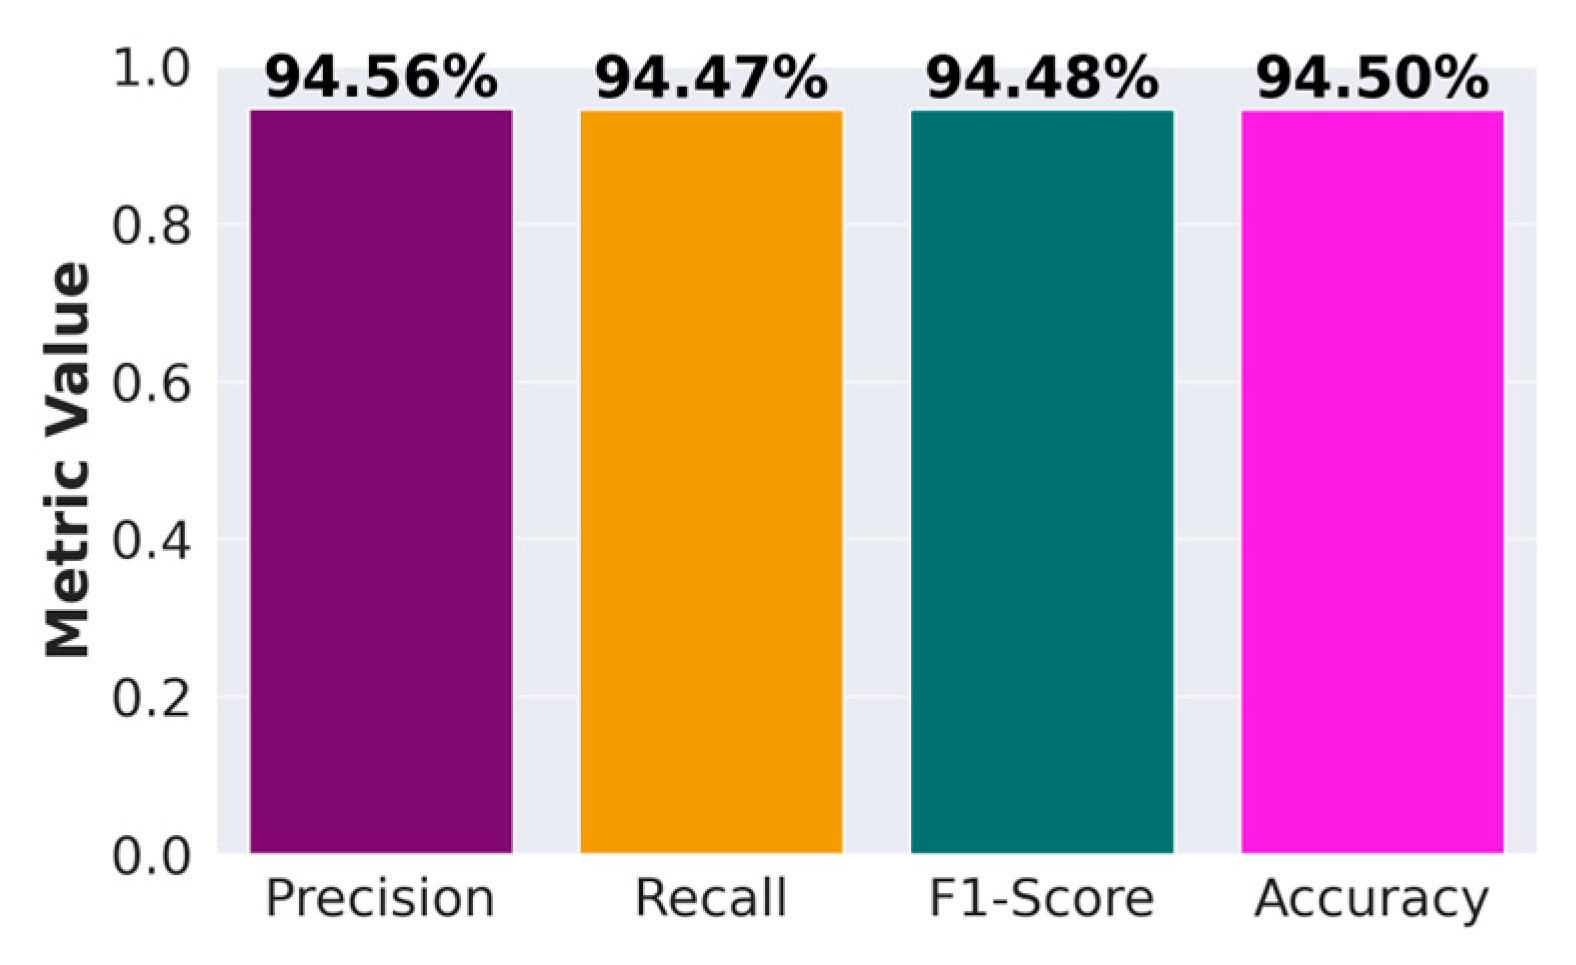

First, we present the results associated with cancer detection for histopathological images. In the context of evaluating the performance of classification models within machine learning, the confusion matrix stands out as a pivotal tool. This matrix provides a detailed breakdown of the predictions made by a model, allowing for a nuanced assessment of its performance in terms of accurately predicting different classes. The confusion matrix is structured as a table, categorizing predictions into four fundamental types: True Positives (TP), True Negatives (TN), False Positives (FP), and False Negatives (FN). TPs and TNs represent instances where the model has correctly predicted the positive and negative classes, respectively. By contrast, FPs and FNs reflect the errors in prediction, where the model incorrectly identifies the positive and negative classes.

Derived from the confusion matrix, several key performance metrics that offer insights into different aspects of the model’s predictive accuracy are accuracy, precision, recall, and F1 score. These metrics, derived from the confusion matrix, are instrumental in comprehensively understanding the performance of a classification model. They highlight not only the model’s accuracy but also the nature and extent of any prediction errors, thereby guiding further model refinement and optimization.

We had 750 images in total representing three different classes and an even distribution of 250 images for each class. We reserved 15% of the data for validation, and the results presented are based on this validation data performance.

Figure 5 presents the confusion matrix for ATT-DenseNet implementation along with two other baselines, namely AlexNet and SqueezeNet.

Figure 6 presents a performance comparison of DenseNet, Alexnet, and SqueezeNet. The performance metrics considered are average accuracy, precision, recall and the F1-score.

As we can see from the presented confusion matrices in

Figure 5, very few samples have been misclassified by the DenseNet compared to the baselines.

Figure 6 provides a figure showing the performance of DenseNet against AlexNet and SqueezeNet in terms of accuracy, precision, recall, and F1 score. For all the performance metrics, DenseNet performs better. DenseNet’s architecture allows for each layer to have direct access to the gradients from the loss function and the original input signal, leading to more efficient training and feature reuse. This is particularly useful in histopathological image analysis, where subtle features and patterns are crucial for accurate classification. Furthermore, in DenseNet, each layer receives a “collective knowledge” from all preceding layers, which improves the flow of gradients throughout the network. This leads to better learning and performance, as each layer can learn more complex features based on all previous layers. To further improve the performance, as presented in

Section 3, we adopt ATT-DenseNet, which is our proposed method. We achieved the following performance (

Figure 7), which surpasses the traditional DenseNet, AlexNet and SqueezeNet.